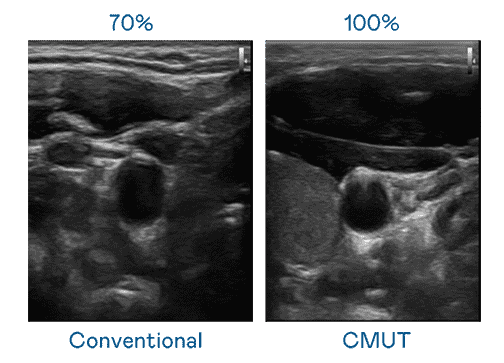

CMUT 技术是一种用电容式微机电元件来产生超音波讯号的技术。。。与传统 PZT 压电式技术相比,,CMUT 频宽增加 30%,,更宽频的超音波讯号让影像解析度大幅提升,,,,是实现高影像品质医疗超音波扫描、、、、促进精准医疗发展的关键技术。。。。

大频宽带来超清晰影像

超音波影像的解析度高低,,首先取决于探头能发出的讯号频宽。。。尊龙集团 CMUT 可提供高清晰的超音波讯号,,提供高频宽、、、高灵敏度、、、、影像纹理细节更高的超音波影像,,,协助医护人员缩短影像判读时间及利用精准的医疗影像进行诊断。。